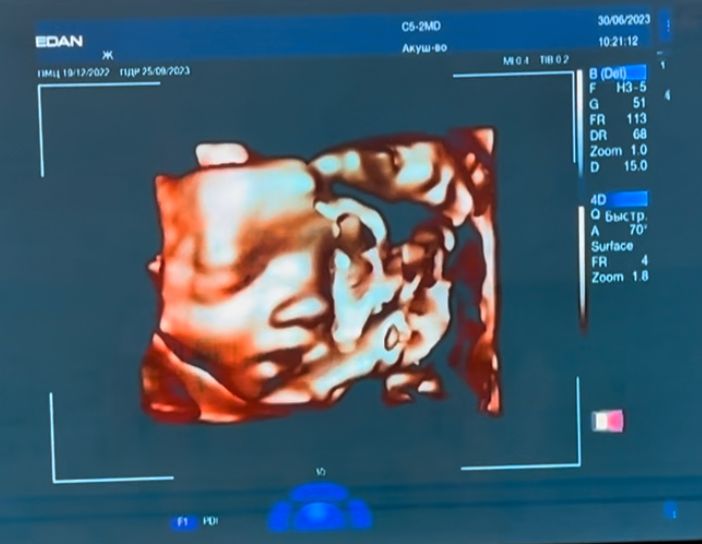

Видела Сашку на 3Д узи. Возле лица обе ноги, пуповина, поэтому полностью лицо запечатлеть не удалось. Но хоть что-то 😁 У нее там все гуд. 1200 гр и 35 см уже. Все показатели в норме, чуть опережает по сроку. Шейка 39мм. Прибавка у меня 10,7 кг. Отеков нет.